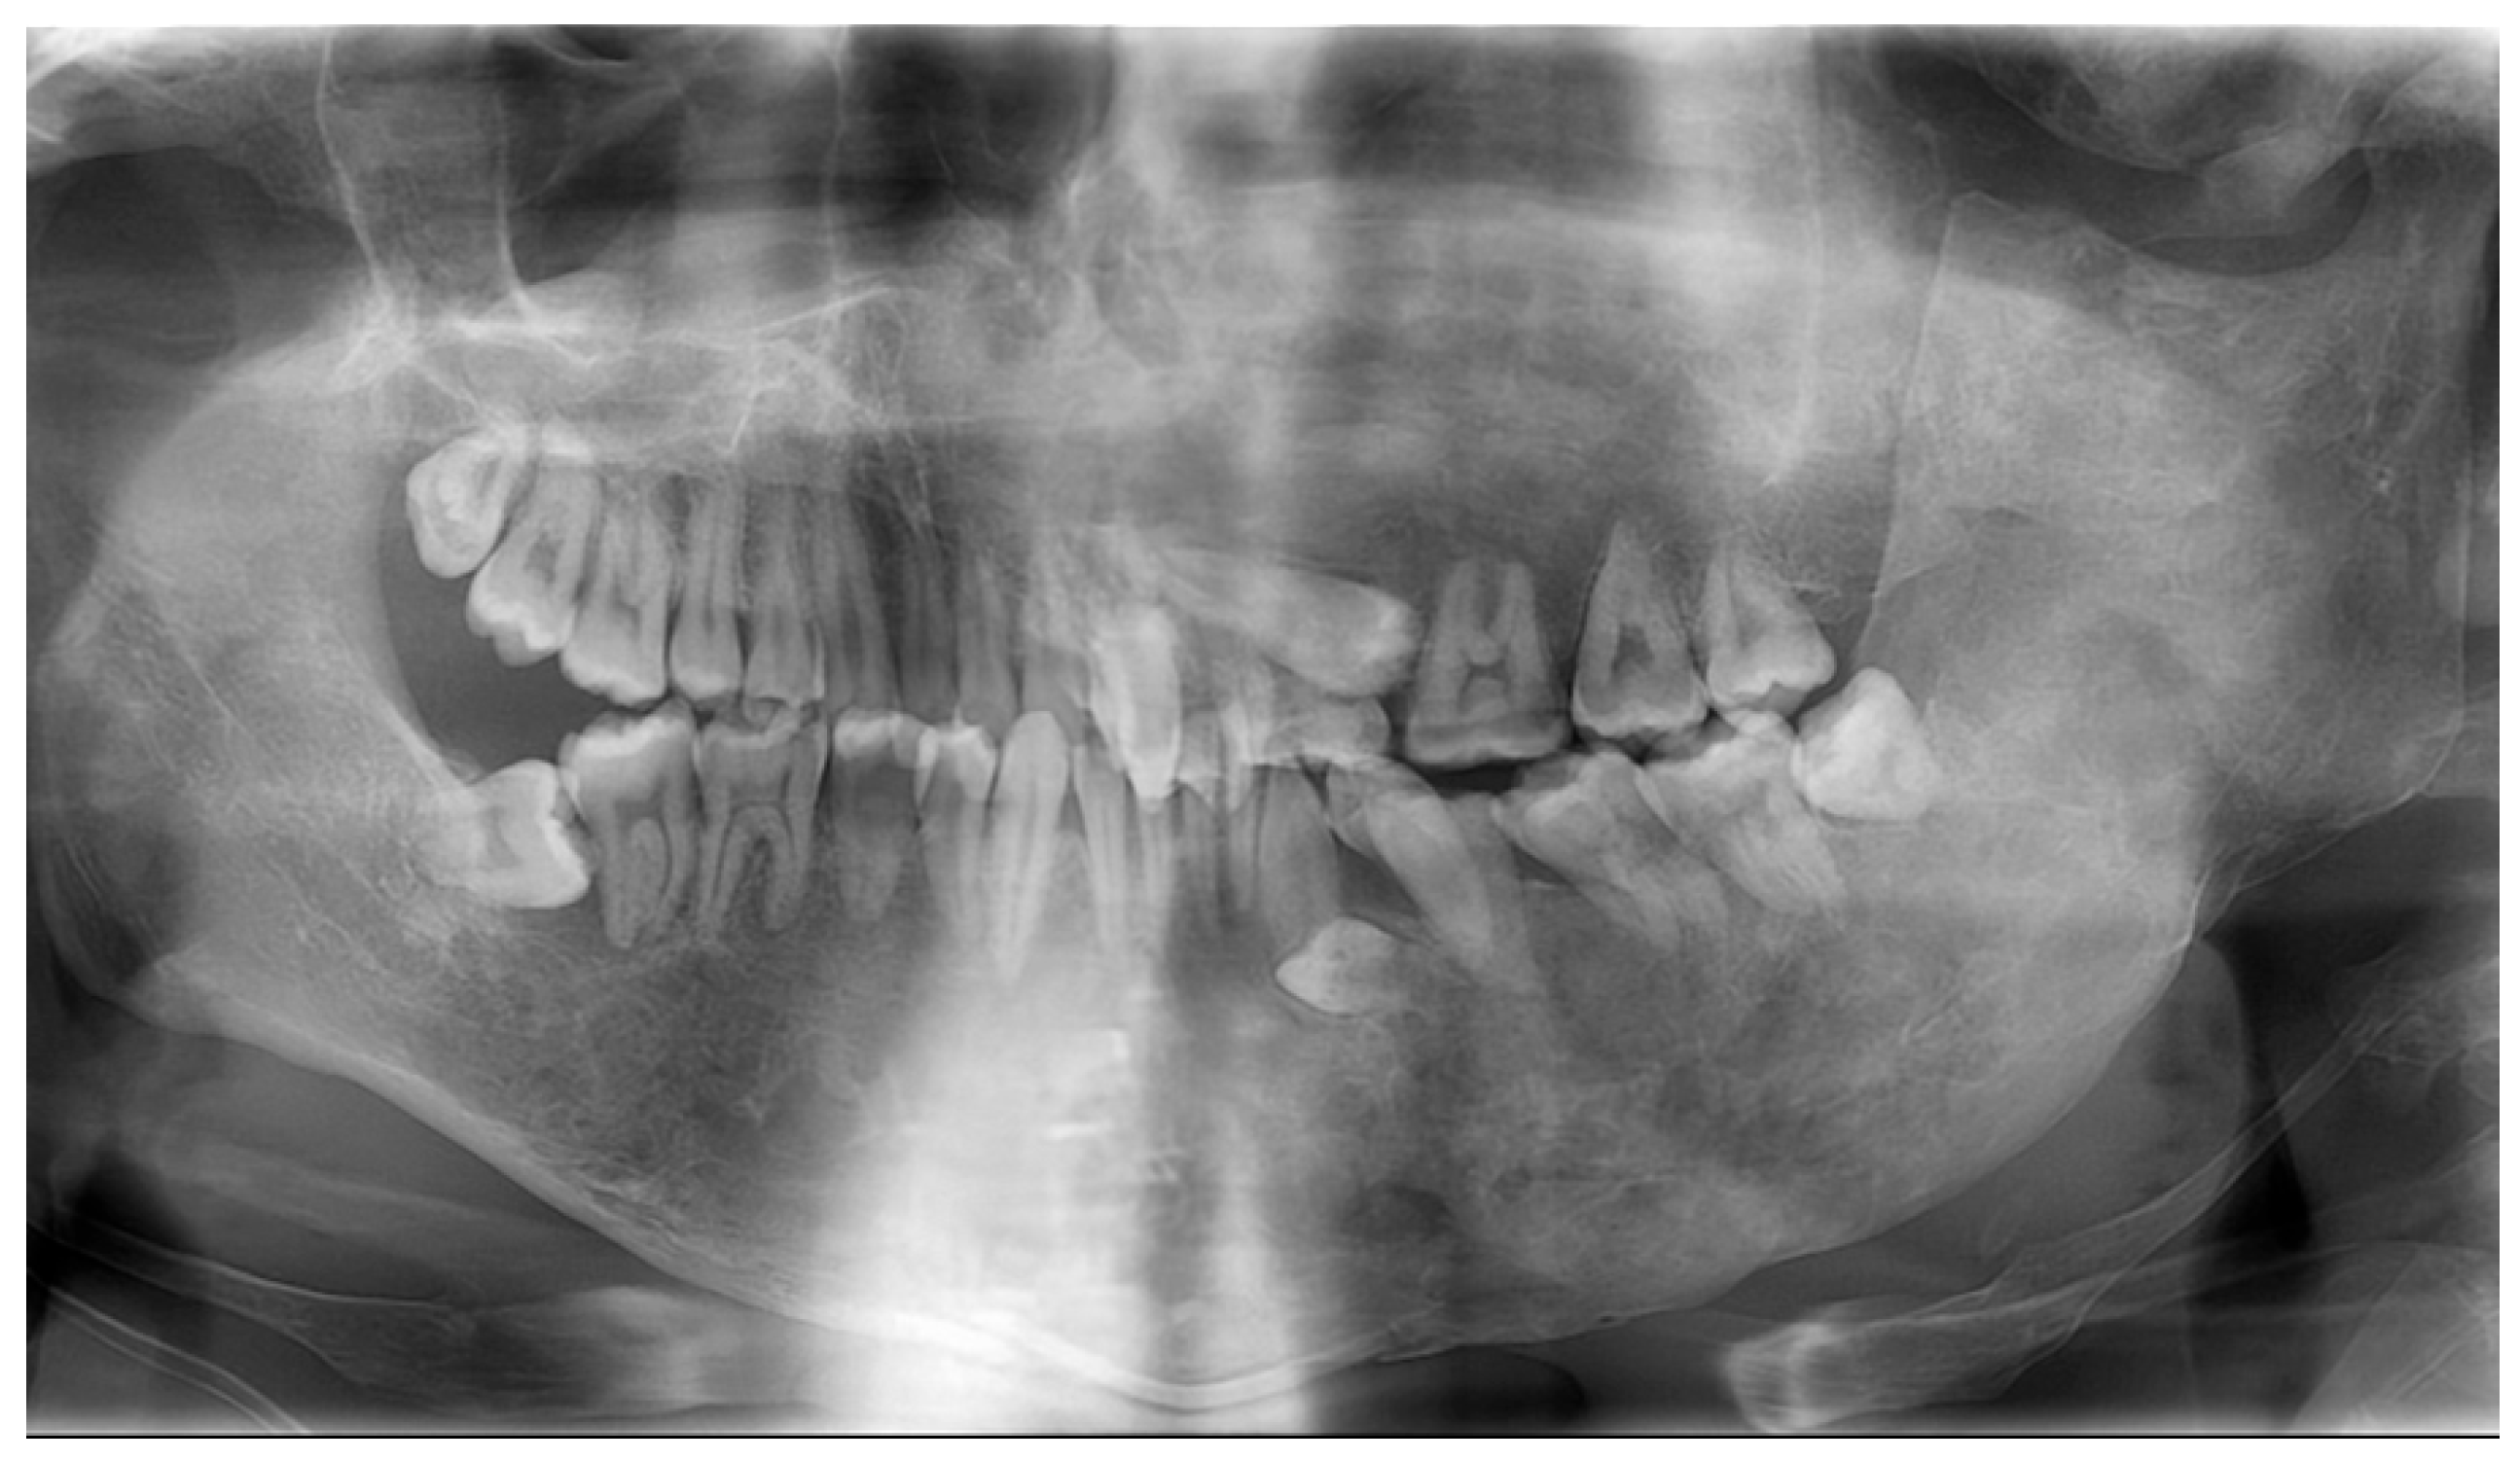

| Age | Occurrences |

|---|---|

| 5 y | Swelling in the left cheek region |

| 9 y | Diagnosis of MAS and precocious puberty, and start of bisphosphonate therapy |

| 11 y | Optic canal decompression surgery |

| 13 y 7 m | First visit to our department |

| 15 y 6 m | Left maxillary primary first molar extraction |

| 19 y 5 m | Discontinuation of bisphosphonate therapy |

| 19 y 9 m | Maxillary and mandibular osteotomies |

| 24 y 10 m | Left mandibular primary second molar extraction |

| 30 y 3 m | Left mandibular primary canine extraction |